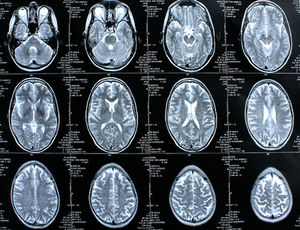

Gehirn-Scans: deutlich mehr Tumore bei Akademikern. Bild: pixelio.de, Rike